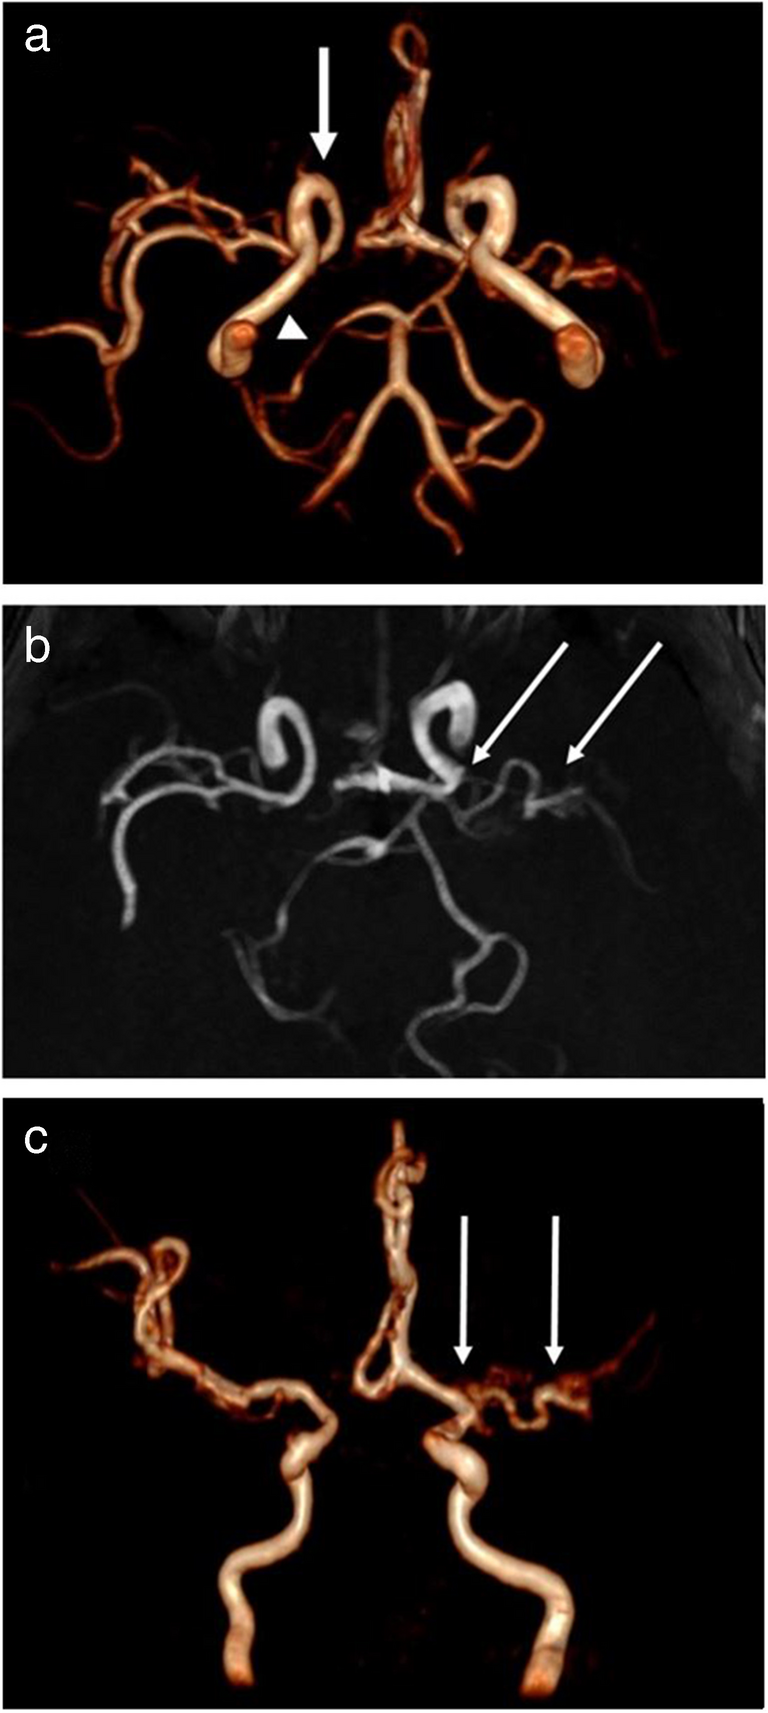

Fig. 1

Brain magnetic resonance imaging in a 15-month-old girl with Aicardi-Goutières syndrome. a Axial T1-weighted image without contrast showing delayed myelination. b Axial T2-weighted image, at the same level, showing hypersignals in the periventricular white matter

The girl underwent successive brain imaging. At 15 months of age, the spinal-cord magnetic resonance imaging (MRI) findings were normal, and brain MRI revealed delayed myelination and T2 hypersignals in the periventricular white matter (Fig. 1). At 2 years and 6 months of age, brain MRI additionally revealed symmetrical clusters of hyposignals on susceptibility-weighted images, suggesting calcifications in the periventricular frontal white matter. Therefore, brain computed tomography (CT) was performed (at the age of 3 years and 2 months), and the findings confirmed the scattered calcifications in the periventricular frontal white matter and in the lenticulate nuclei (Fig. 2). These results suggested Aicardi-Goutières syndrome or pseudo-TORCH syndrome; however, TORCH infections were excluded. Trio-based whole-genome sequencing revealed a homozygous p.Arg290 Cys variant in the SAMHD1 gene (Chr20(hg38):g.36917034G>A;NM_015474.4:c.868 C>T). Each parent was heterozygous for the variant. This variant has previously been reported in a patient with interferonopathy and was considered pathogenic (class 5 according to the American College of Medical Genetics and Genomics) [3]. This finding led to the performance of another brain MRI with 3D time-of-flight (TOF) angiography at 4 years and 3 months of age, which revealed severe stenosis of the left middle cerebral artery origin, with a dilated collateral arterial network (moyamoya syndrome); long stenosis of the right posterior cerebral artery; and mild narrowing of the right internal carotid artery (Fig. 3). No ischaemic lesions were detected on diffusion-weighted, T1-weighted, or T2-weighted images. Even retrospectively, no obvious intracranial arterial stenosis was visible on conventional MRI sequences. Retrospectively, brain CT revealed mild hypoplasia of the right carotid canal at the level of the petrous bone (Fig. 2). The narrowing of the right internal carotid artery was considered a congenital anomaly (i.e., hypoplasia) rather than an acquired process (i.e., stenosis).